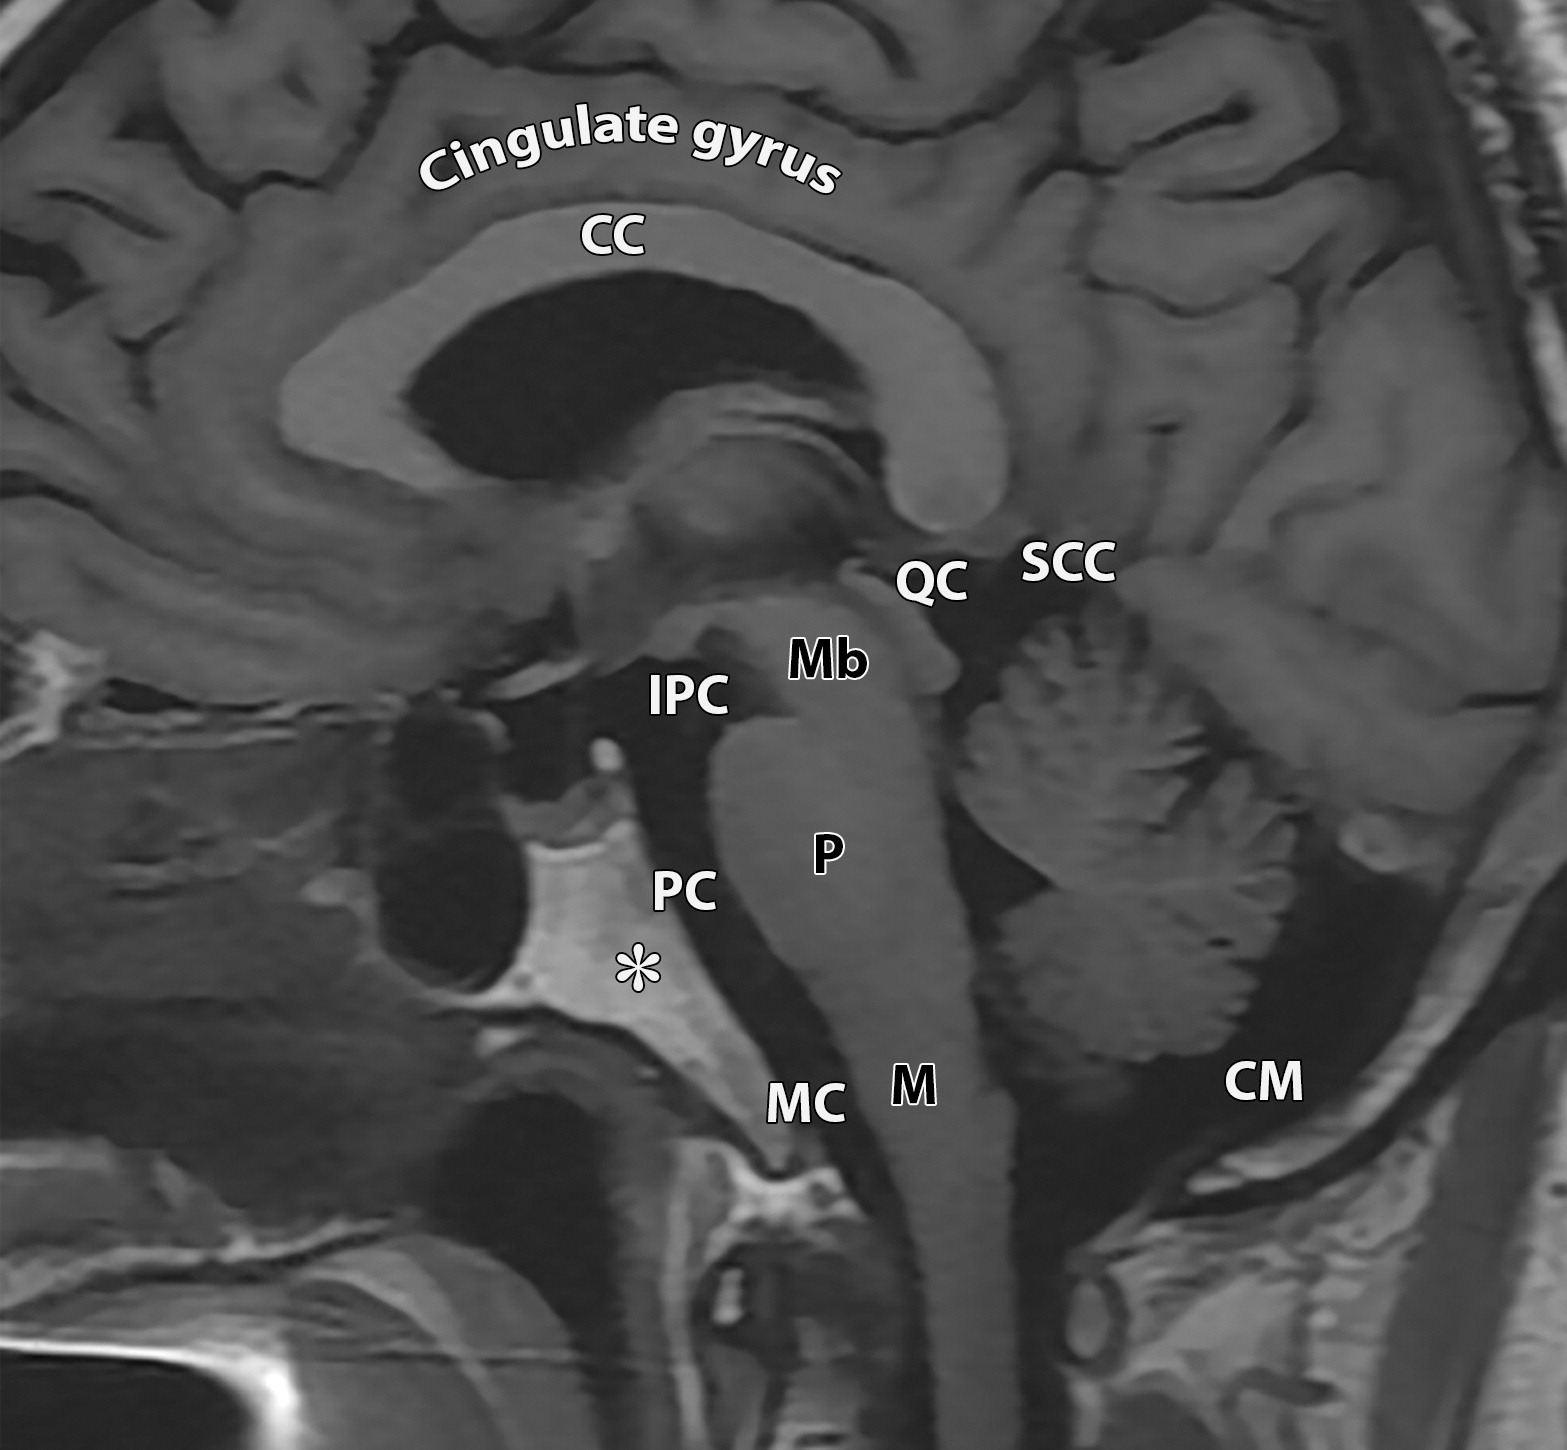

枕大池(CM),脚间池(IPC),延髓池(MC),脑桥池(PC),四叠体池(QC),小脑上池(SCC),胼胝体(CC),扣带回(cingulate gyrus),斜坡(*),脑干组成:中脑(Mb),脑桥(P),延髓(M)。